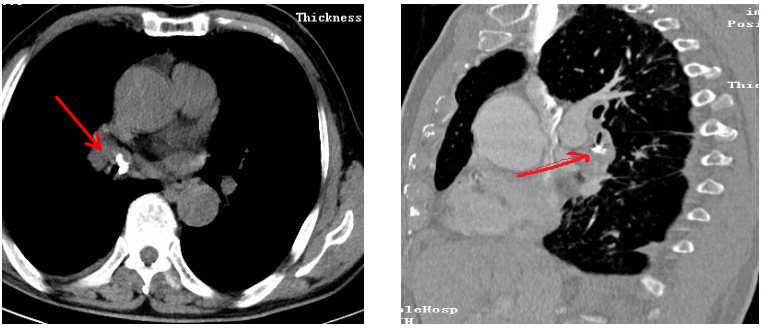

70多岁的殷大爷近二个月来反复出现咳嗽、咳痰伴呼吸困难,服用很多药物后病情仍未见好转,严重影响了他的生活,深受病痛折磨的他于近日来到县人民医院呼吸与危重症医学科检查。入院后接诊的温大夫立即给他完善了胸部CT检查,检查提示双肺炎性病变;右肺门增大,建议治疗后复查及增强扫描。入院诊断考虑肺炎、肺部占位待排,拟进一步行支气管镜检查。在进行支气管镜常规术前讨论时,在万钧博士带领下,科室全体医护人员对殷大爷的病史进行了仔细认真的讨论,考虑为气管异物的可能性大。在反复追问殷大爷,他对自己是否有进食呛咳的情况完全没有印象。我们又进行了进一步检查,胸部增强CT显示右肺中间段支气管腔内高密度影,异物可能。

因异物对气管的损伤,患者反复出现肺部感染,且出血的风险较大,但这种情况需尽早将其取出,否则患者的感染得不到有效的控制,且异物的长期存在将产生更严重的后果。在与家属沟通后,该科做了充分的术前准备,于2020年6月17日下午为殷大爷进行了支气管镜检查。不出所料,镜子下可以清晰的看到右肺中间段支气管处有一异物阻塞管腔,周围已经有肉芽组织生成。万钧博士用他精湛的气管镜技术,终于将“罪魁祸首”取出,这是一块不规则的骨性异物(如下图),如果不及时取出,很有可能因为尖锐外形穿破气管、血管等可导致致命性大出血、或感染迁延不愈。